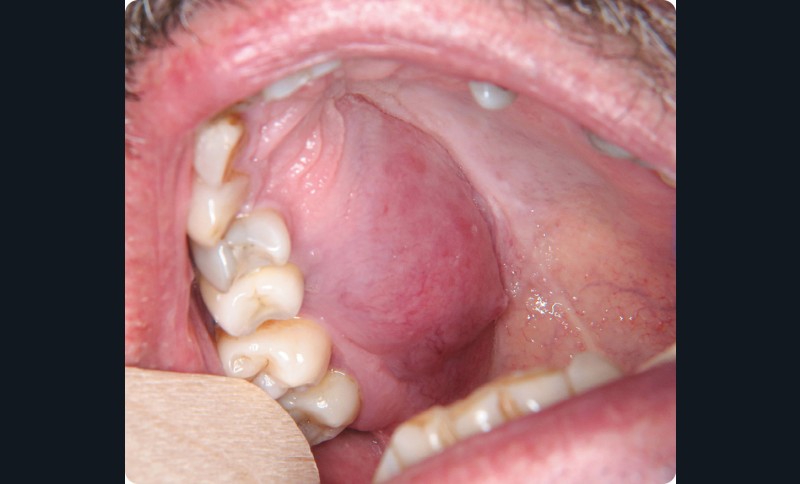

- On observait une tuméfaction oblongue, étendue sur l’hémi-maxillaire droit de 13 à 17, côté palatin. à la palpation, la lésion était rénitente.